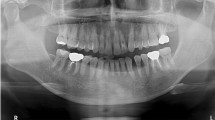

In this paper, a new powerful deep learning framework, named as DENTECT, is developed in order to instantly detect five different dental treatment approaches and simultaneously number the dentition based on the FDI notation on panoramic X-ray images. This makes DENTECT the first system that focuses on identification of multiple dental treatments; namely periapical lesion therapy, fillings, root canal treatment (RCT), surgical extraction, and conventional extraction all of which are accurately located within their corresponding borders and tooth numbers. Although DENTECT is trained on only 1005 images, the annotations supplied by experts provide satisfactory results for both treatment and enumeration detection. This framework carries out enumeration with an average precision (AP) score of 89.4% and performs treatment identification with a 59.0% AP score. Clinically, DENTECT is a practical and adoptable tool that accelerates the process of treatment planning with a level of accuracy which could compete with that of dental clinicians.

The use of artificial intelligence (AI) in dentistry has become a topic of great interest as it gradually takes part in more and more dental papers throughout recent years1. From simpler situations like classifying oral malodor to more serious matters like predicting the progression of oral cancer, we see that AI is indeed impacting the workfield for dentists2, 3. In addition to that, a particular area of importance for dental practitioners is the field of radiology. Dental practitioners deal with radiology in their day-to-day practice by taking panoramic X-rays of the oral cavity before, during, and after treatments. This yields them with an essential diagnostic aid that provides evidence of pathologies that are not always seen with the naked eye such as dental caries, periapical lesions, or odontogenic cysts. Since dental radiography has a significant role in patient care, we expect that reinforcing it with AI would increase the accuracy of the diagnosis and treatment plan substantially.

One of the most common obstacles of radiological interpretation are perceptual errors which account for 60–80% of misdiagnosis4. Panoramic radiographs used by dentists may also be responsible for these diagnostic errors because of the multiple superimpositions and distortions depicted by numerous anatomical structures5. Therefore, misinterpretation during dental radiographic analysis is inevitable, however, we postulate that it can be overcome if AI is utilized during diagnosis and treatment planning. For example, an AI system that could automatically number the dentition and point out the teeth in need of treatment could in turn decrease the likelihood of executing the wrong therapy or even treating the wrong tooth. By way of illustration, in one study6, it was found that the prevalence of wrong tooth extraction is 21.1% because of common issues like miscommunication and exhaustion of overworking dentists. Thus, we highly believe that pairing an AI mechanism with dental radiology would help dental practitioners overcome these problems in the clinical setting as well as assist them in carrying out procedures in a more precise manner or with a low margin of error.

Dental radiography is an essential tool that is frequently used by dentists to apprehend the general condition of the patient. Among many imaging techniques, panoramic radiography is most commonly chosen for use because it offers greater patient acceptance and cooperation with a minimal dose of radiation. Due to its simple and painless procedure, patients are able to comply to the care provided. For most patients, a dental radiograph is requested because some diseases are not always seen with the unaided eye. Despite this advantage, it is still quite common for dental practitioners to make clinical errors regarding the diagnosis and treatment. If a system that could simultaneously number the dentition and indicate the teeth that need intervention were to be incorporated into the clinical setting, these errors could be significantly reduced. The present study brings these two aspects together to positively impact the clinical experience for dentists.